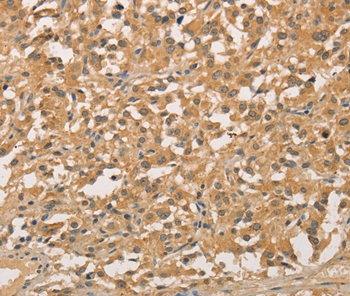

Immunohistochemical analysis of paraffin-embedded Human thyroid cancer tissue using #35844 at dilution 1/20.